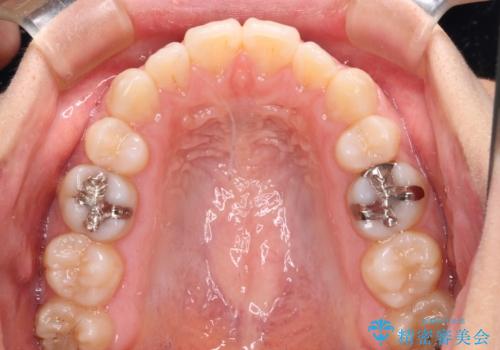

- インビザライン・ライト

インビザライン・ライトは提供されるマウスピースの数に制限があり、通常のタイプよりもマウスピース提供期間が短くなっている一方、安価に治療を行うことができるプランです。

治療のゴールも変更できないため、軽微な歯列不正や、後戻り改善などに適しています。